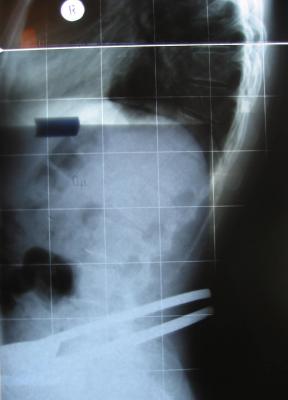

Röbis Im KOrsett

Wie gesagt, Röbis im KOrsett

- korset3.jpg (7.92 KiB) 7662 mal betrachtet

- korsett2.jpg (8.4 KiB) 7662 mal betrachtet

- korsett1.jpg (8.86 KiB) 7662 mal betrachtet